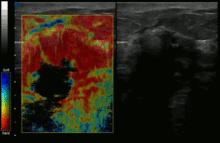

![]() Conventional ultrasonography (lower image) and elastography (supersonic shear imaging; upper image) of papillary thyroid carcinoma, a malignant cancer. The cancer (red) is much stiffer than the healthy tissue. | |

Supersonic Shear Imaging (SSI)

Supersonic Shear Imaging (SSI)[7][8] gives a quantitative, real-time two-dimensional map of tissue stiffness. SSI is based on SWEI: it uses acoustic radiation force to induce a 'push' inside the tissue of interest generating shear waves and the tissue's stiffness is computed from how fast the resulting shear wave travels through the tissue. Local tissue velocity maps are obtained with a conventional speckle tracking technique and provide a full movie of the shear wave propagation through the tissue. There are two principal innovations implemented in SSI. First, by using many near-simultaneous pushes, SSI creates a source of shear waves which is moved through the medium at a supersonic speed. Second, the generated shear wave is visualized by using ultrafast imaging technique. Using inversion algorithms, the shear elasticity of medium is mapped quantitatively from the wave propagation movie. SSI is the first ultrasonic imaging technology able to reach more than 10,000 frames per second of deep seated organs. SSI provides a set of quantitative and in vivo parameters describing the tissue mechanical properties: Young’s modulus, viscosity, anisotropy.

This approach demonstrated clinical benefit in breast, thyroid, liver, prostate and musculoskeletal imaging. SSI is used for breast examination with a number of high-resolution linear transducers.[9] A large multi-center breast imaging study has demonstrated both reproducibility [10] and significant improvement in the classification[11] of breast lesions when shear wave elastography images are added to the interpretation of standard B-mode and Color mode ultrasound images.